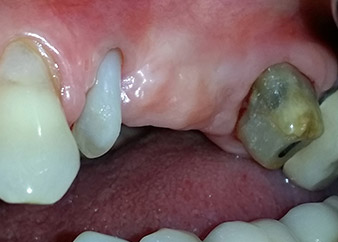

Une patiente de 58 ans se plaignait de douleurs et d'une mobilité accrue de la dent pilier 24 de son bridge. Présence d'une inflammation parodontale avec formation de poches de 7 mm de profondeur dans le sens mésiobuccal et de plus de 12 mm dans le sens distal, ainsi que d'une atteinte de la furcation au troisième degré. La radiographie a par ailleurs révélé une lésion parodontale étendue autour de la région apicale de la dent 24 ayant préalablement reçu un traitement endodontique (alio loco) (Fig. 1).

Un mois plus tard, le jour de l'intervention, la douleur et l'inflammation sur la dent 24 étaient minimes mais une mobilité de classe 2 de Miller était toujours observable. Après ouverture des lambeaux et nettoyage des tissus périapicaux et périradiculaires infectés, l'étendue du défaut osseux est devenue parfaitement visible (Figures 2 et 3).

À la racine de la dent, il manquait la totalité de l'os vestibulaire et distal. L'attache était essentiellement limitée à la racine palatine, venant ainsi confirmer le pronostic défavorable initial. La dent 27 présentait également une attache horizontale réduite et une raréfaction apicale minime (cf. Fig. 1), sans symptômes cliniques.